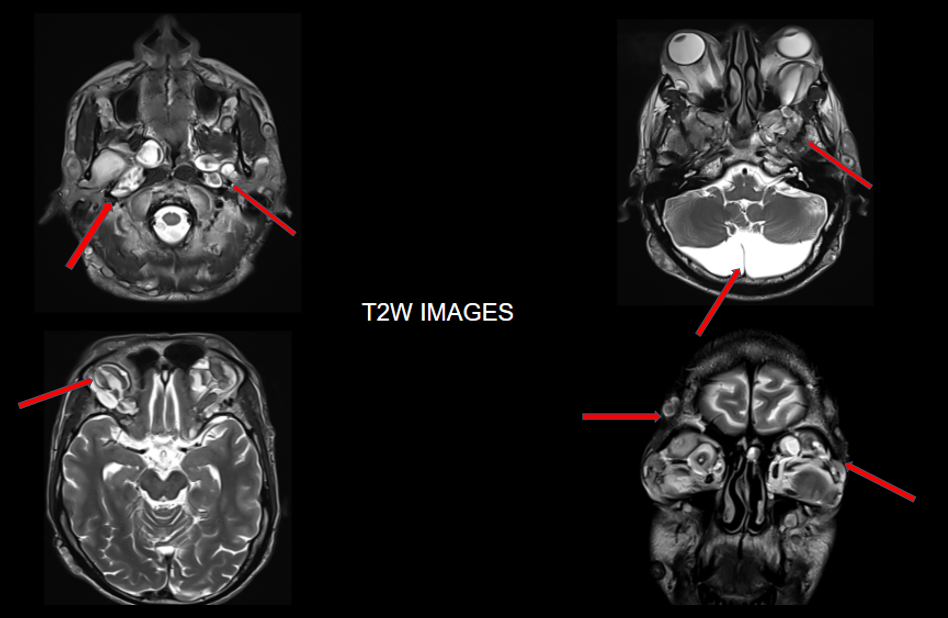

FINDINGS – MRI BRAIN WITH IV CONTRAST

Multinodular T2 hyperintense hypointense transpatial lesions seen within the bilateral orbits occupying the intra and extraconal spaces with targetoid appearance.

The lesion extends through the inferior orbital fissure into the pterygopalatine fossa bilaterally.

The lesions also extend through the foramen ovale into the superior aspect of masticator space bilaterally.

Similar heterogeneously enhancing nodular lesions are also seen bilateral fronto-temporal and occipital scalp regions. Incidental retrocerebellar arachnoid cyst.

Lesion extends into the orbital apex and along the bilateral cavernous sinuses.

Similar heterogeneously enhancing nodular lesions are seen extending into the upper neck in bilateral parotid and the visualised level II regions.

The lesions show heterogenous post-contrast enhancement.

Extensive orbitofacial plexiform neurofibroma.

They are best visualised on fat suppressed T2 weighted MR imaging where they appear as hyperintense masses with or without multiple target signs.

They demonstrate mild enhancement with IV gadolinium and are isointense on T1 signal.